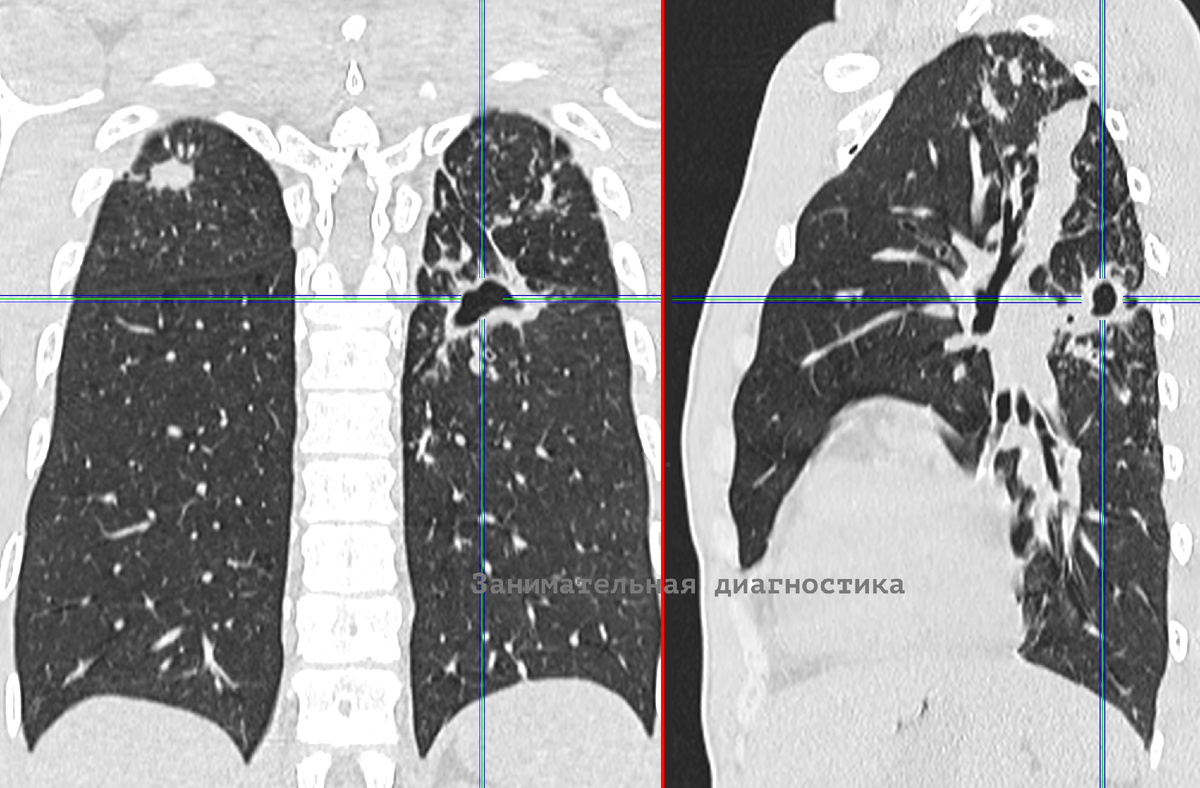

Молодой мужчина 32 лет обратился с жалобами на слабость, длительный кашель и невысокую температуру.

На КТ выявлен двухсторонний воспалительный процесс в лёгких, преимущественно в верхних долях, полость распада в нижней доле левого лёгкого.

Налицо типичная картина запущенного туберкулёза.